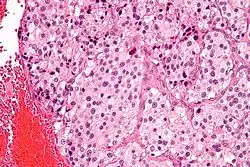

| Micrograph of a carotid body tumor (a type of paraganglioma) | |

On microscopic inspection, the tumor cells are readily recognized. Individual tumor cells are polygonal to oval and are arranged in distinctive cell balls, called Zellballen.[9] These cell balls are separated by fibrovascular stroma and surrounded by sustentacular cells.

By light microscopy, the differential diagnosis includes related neuroendocrine tumors, such as carcinoid tumor, neuroendocrine carcinoma, and medullary carcinoma of the thyroid.

With immunohistochemistry, the chief cells located in the cell balls are positive for chromogranin, synaptophysin, neuron specific enolase, serotonin, neurofilament and Neural cell adhesion molecule; they are S-100 protein negative. The sustentacular cells are S-100 positive and focally positive for glial fibrillary acidic protein. By histochemistry, the paraganglioma cells are argyrophilic, periodic acid Schiff negative, mucicarmine negative, and argentaffin negative.

Micrograph of a carotid body tumor -

S100 immunostain highlighting the sustentacular cells in a paraganglioma -